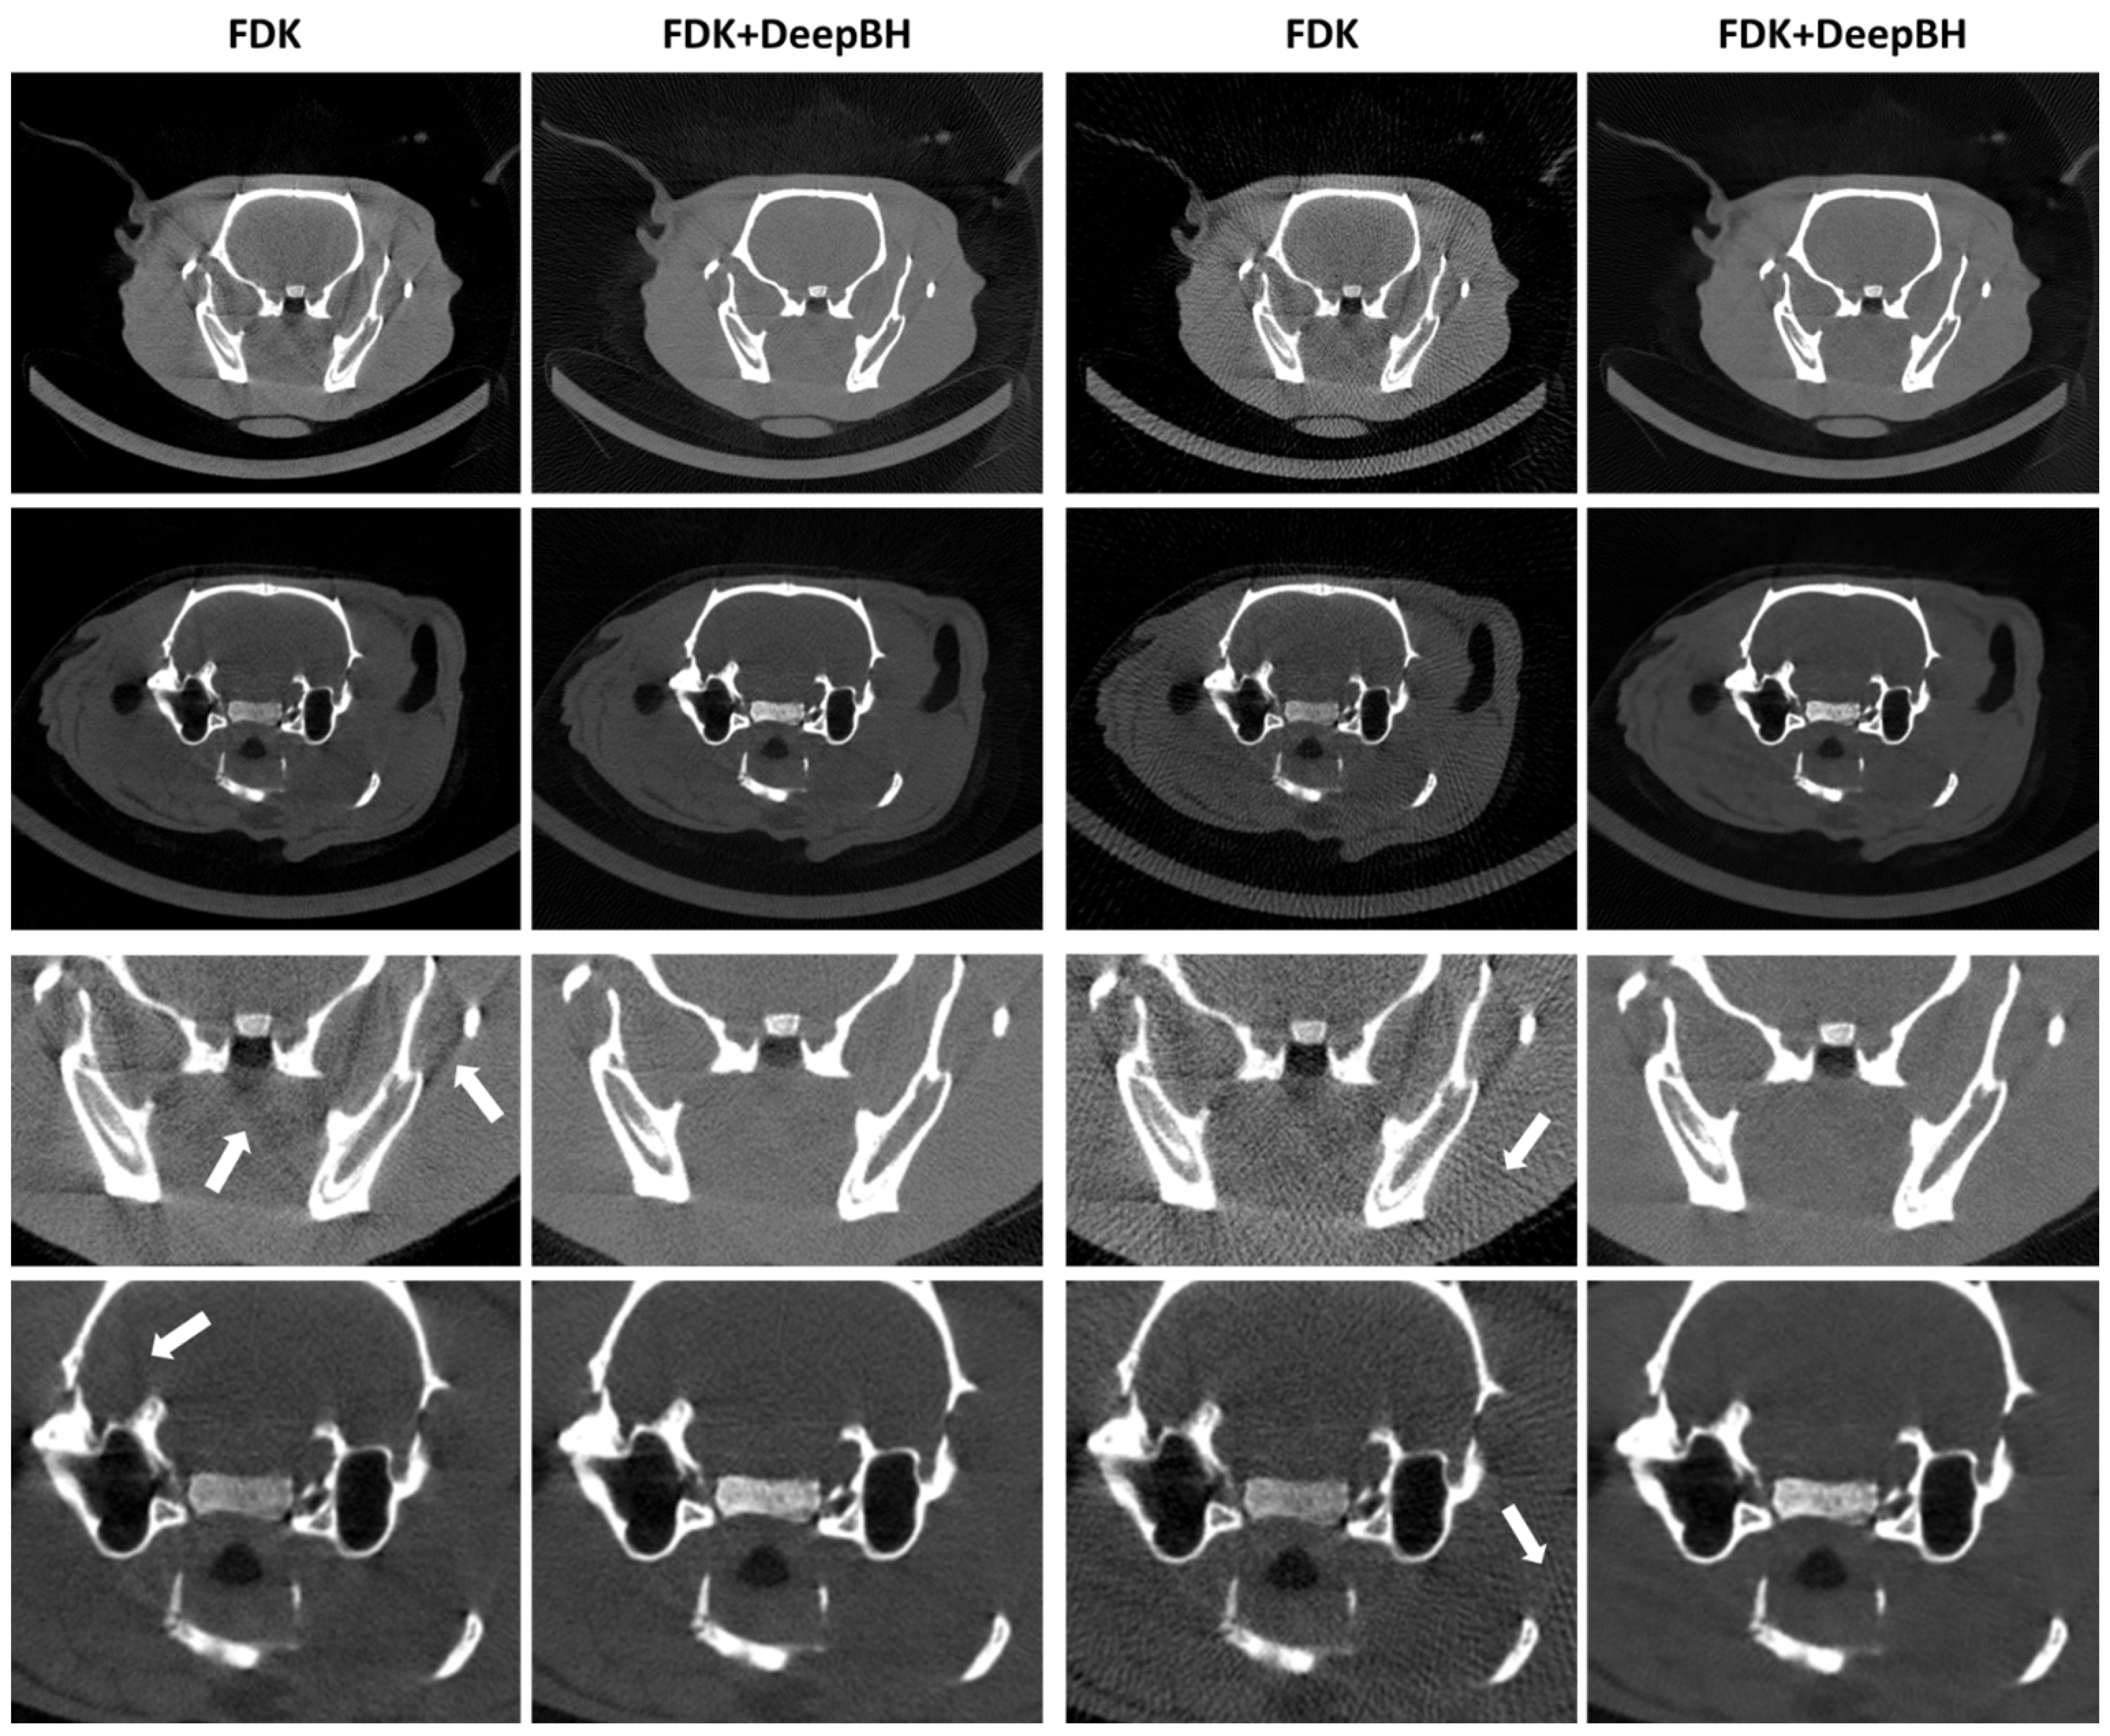

Results for the SD and LD scenarios showed that a postprocessing step with DeepBH was able to correct both streaks and dark band artifacts, with a result very similar to the target regardless of the dose (Figure 4). This is quantitatively supported by the improvement in PSNR and SSIM values, especially for the LD scenarios due to the elimination of streaks (Figure 5).

Figure 4.

Top: central axial slices of the FDK reconstructions scenarios and DeepBH results for SD and LD scenarios for the two test studies. Bottom: zoomed-in images. Arrows in zoomed-in images point to beam hardening (first column) and streaks (third column).